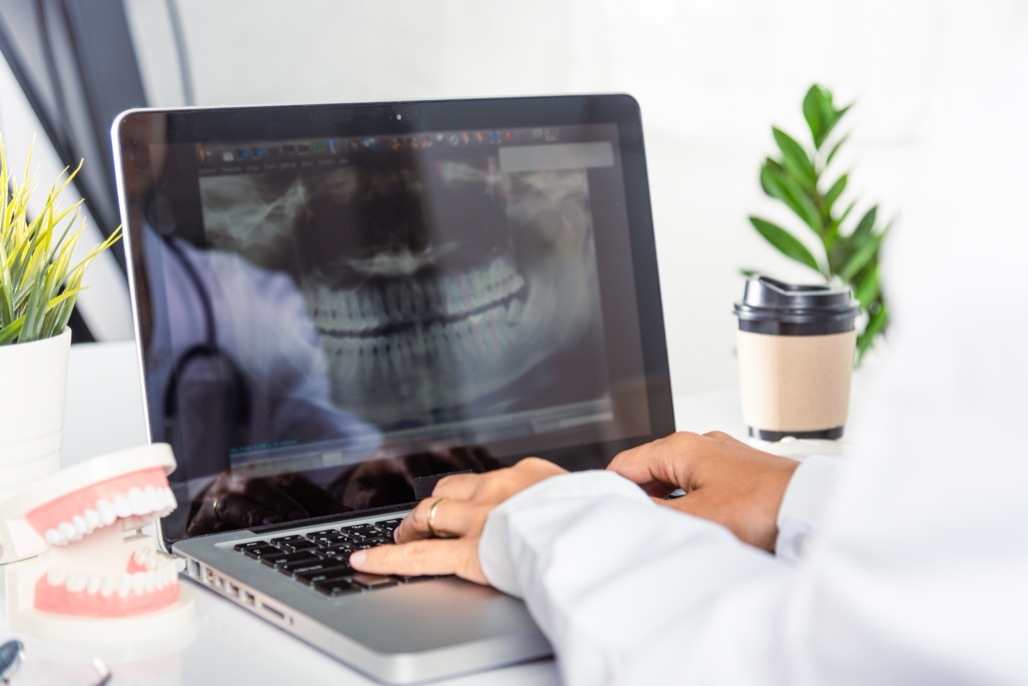

Dental Implants Dental implants are considered the standard of care for prosthetic replacement of missing teeth. A dental implant is an artificial tooth root surgically fixed into the jawbone to hold a crown or dental bridge in order to complete the structure of an artificial tooth. A tooth consists of a root and a crown. …

Dental Implants Simply put, a dental implant is an artificial tooth root. A dental implant takes the place of an extracted tooth root. The root is surgically placed to hold an artificial tooth such as a crown or bridge. Most dental implants are made of titanium, a few are ceramic. Titanium and ceramic are safe …